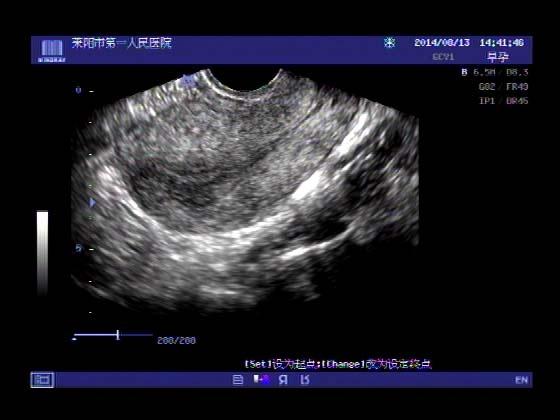

超声入门贴341:宫外孕(阴超的魅力)

女,32岁,停经15天,

一周前在上极医院检查:化验尿HCG阳性,血HCG400多,超声检查问见明显孕囊,让随访。

很典型,图像不错,阴超的优势!!

看见卵黄囊啦~孕囊型的吧?